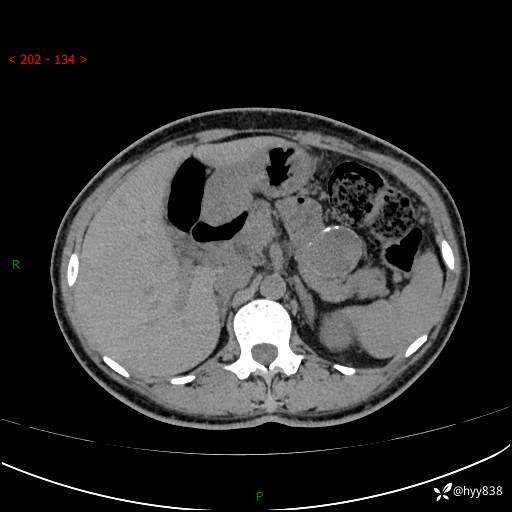

增强动脉期+静脉期

img